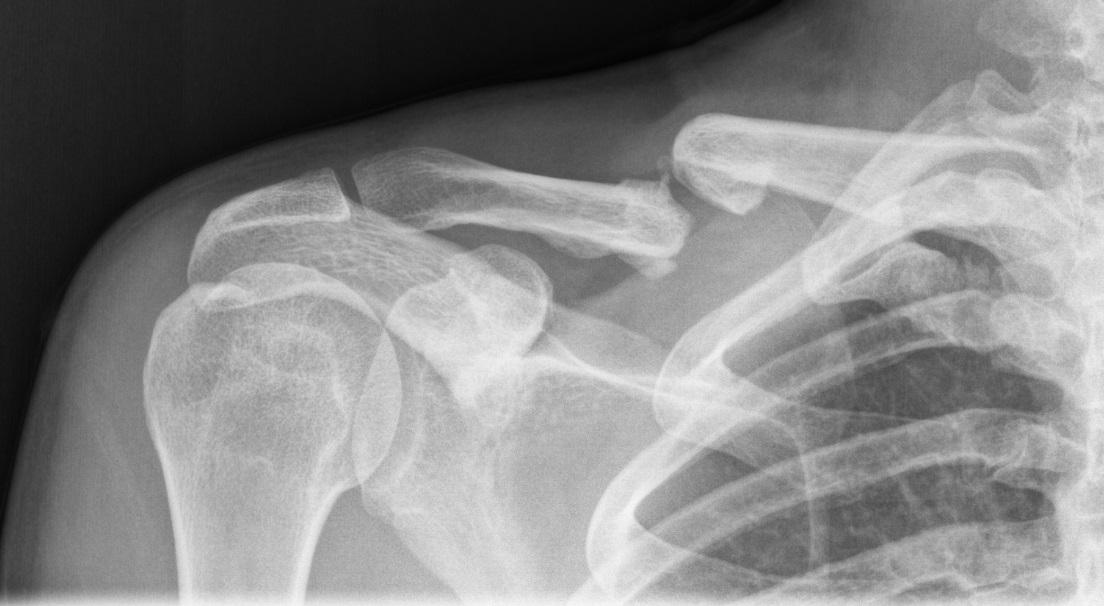

In pieces Clavicle fracture Radiology Key